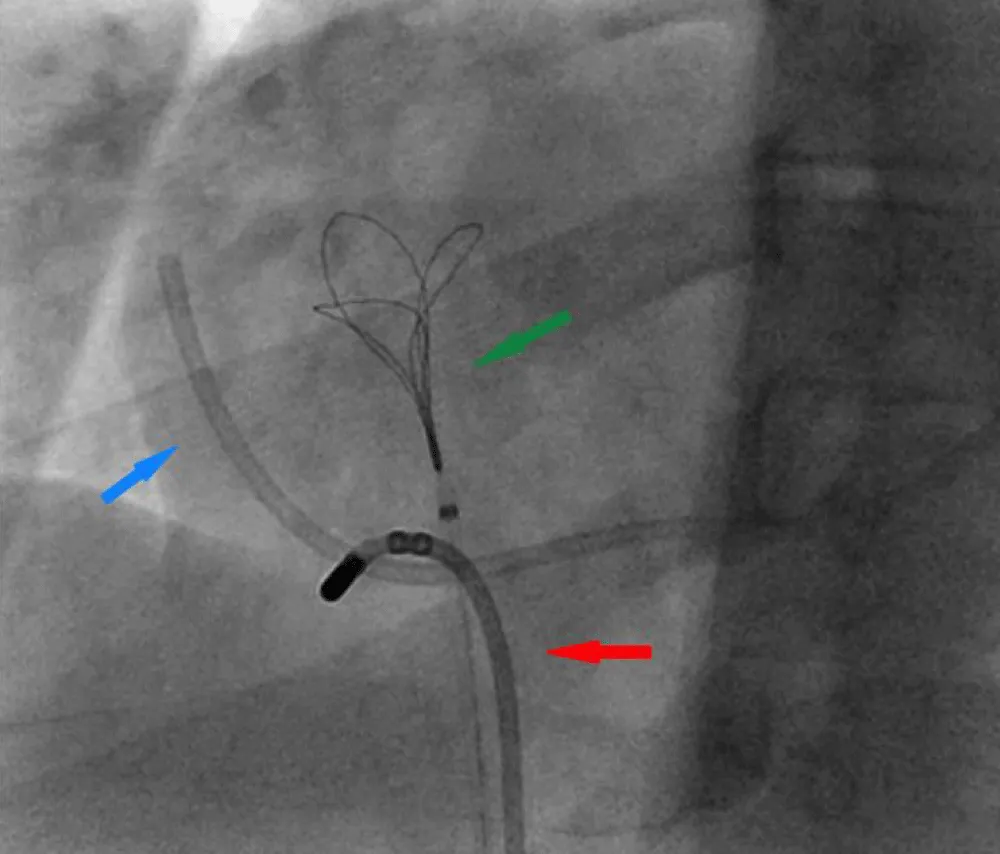

This maneuver freed the right atrial end of the port, for which the endovascular snare was then used with success. The fractured port was finally retrieved as one unit (Figure 4 and Video 2 Click here.

Figure 4: Right Heart catheterization showing Endovascular snare retrieving the freed end of the port. Fractured Port (blue arrow), Navigational steerable catheter (red arrow), Snare (green arrow).